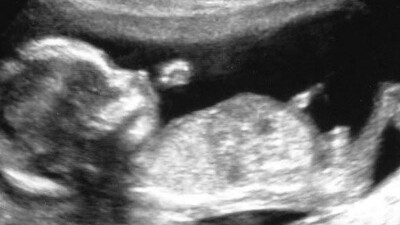

Bebeğiniz bu haftadan itibaren solunum yapma çalışmalarına hız verir. Gözler ve kulaklar gelişimini sürdürmekte, boyun uzamaktadır. Bebeğin başı daha da hareketlenmiş ve çenesine yaslanmış sabit pozisyonundan kurtulmuştur. Bebeğiniz artık ellerini ve ayaklarını kendi isteğine göre serbestçe hareket ettirmektedir.

Bu hafta sonunda bebeğinizin boyu 10 cm. ve ağırlığı tam 45 gram!